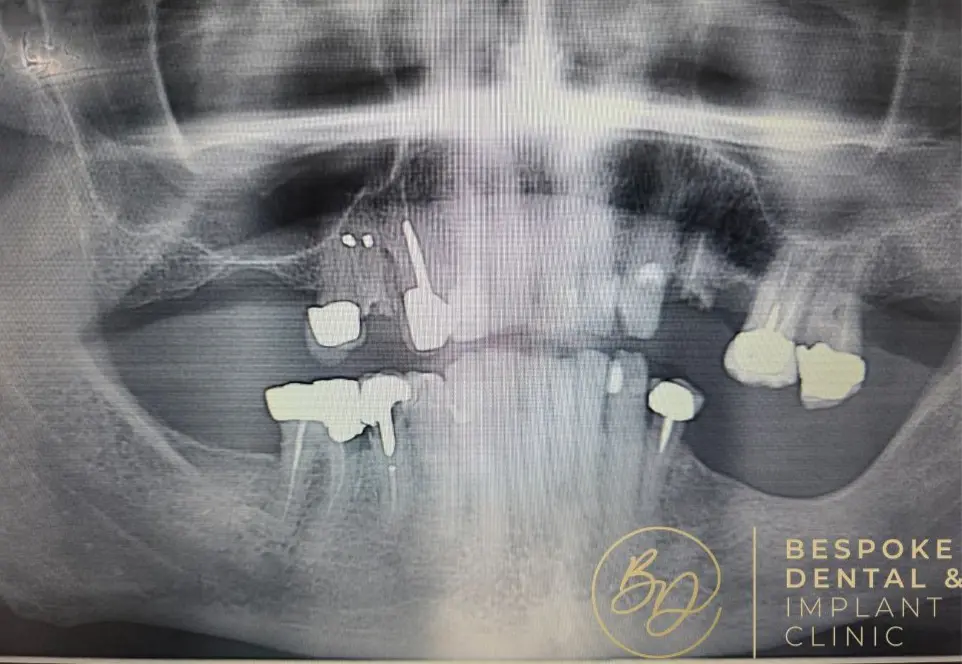

A dental implant is a screw-like metal post inserted into the jawbone. It acts as a natural tooth root and serves as a foundation for the replacement tooth, a custom-made dental crown that sits atop the implant.

Dental implants can also support dentures and bridges and provide a stable set of functional teeth that look and feel completely natural and can last a lifetime.